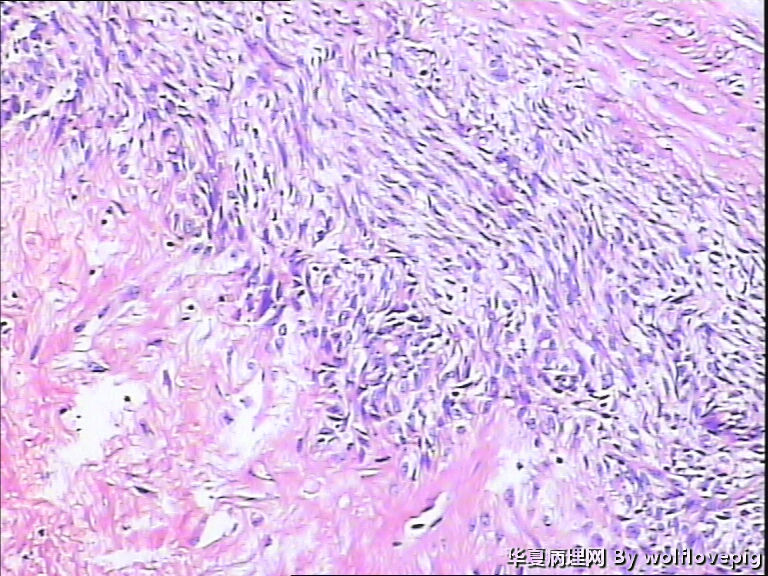

37y,肌壁间可见多个小结节0.2~0.8cm。

图4